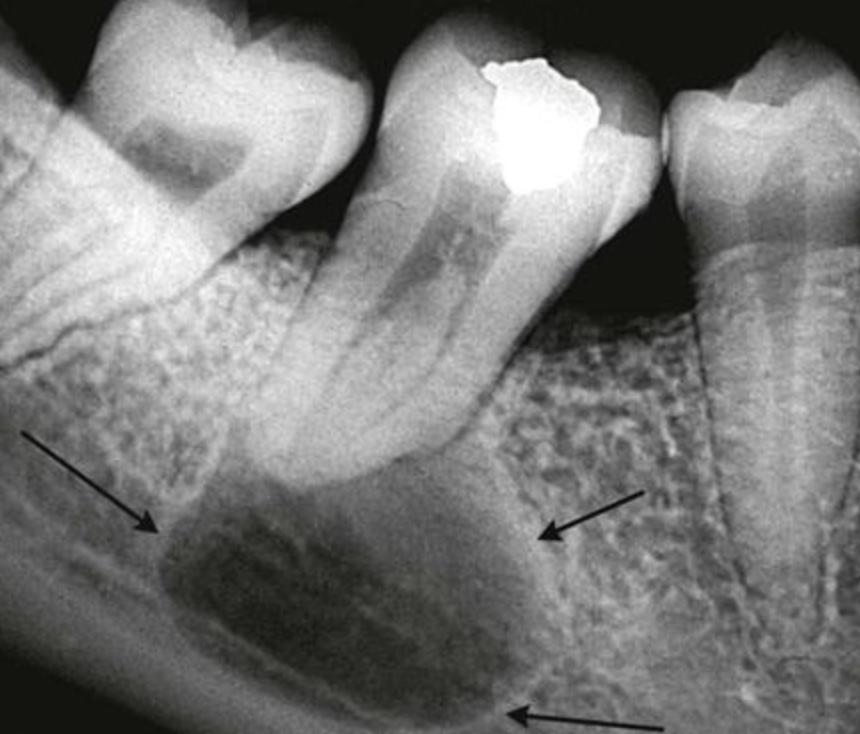

Диагноз "киста" нередко пугает пациентов, которые ассоциируют его с чем-то страшным, вроде новообразования. Особенно жутко становится, когда киста расположена рядом с зубом. Давайте разберемся, действительно ли всё настолько ужасно и есть ли повод для беспокойства. Что такое киста в любом органе у человека❓ Это патологическая полость, которая имеет оболочку и содержимое. Если говорить про кисты, связанные с зубами – так называемые перирадикулярные кисты – то это кисты, которые расположены вокруг корня зуба. И чаще всего причиной их возникновения является хронический периодонтит. Сразу уточним, что не всегда и не обязательно хронический периодонтит со временем переходит в кисту. Но иногда такое случается. Как узнать, что киста есть? На рентгеновских снимках в таких случаях врач может видеть достаточно четкие границы патологического процесса. Это косвенно говорит о том, что, скорее всего, вокруг очага хронического воспаления начала образовываться оболочка, которая впоследствии перерасте